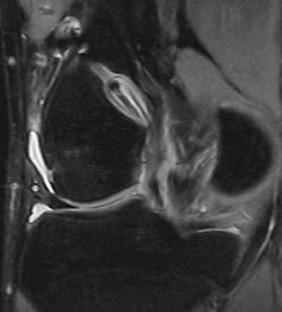

Tunnel enlargement after anterior cruciate ligament (ACL) reconstruction may compromise revision surgery. The cause of this tunnel enlargement is not yet fully understood, but it is thought to be multifactorial, with biomechanical and biological factors playing a role. Tunnel enlargement has been described particularly in patients who underwent ACL reconstruction with hamstring tendons with extracortical fixation devices. The purpose of our study was to evaluate prospectively with magnetic resonance imaging (MRI) the changes in femoral tunnel diameter following arthroscopic anatomic ACL reconstruction with hamstring tendons. At 3-month post-op, all tunnels had enlarged compared to the diameter of the drill and most tunnels enlarged more in the midsection than at the aperture. In the posterolateral tunnels, the entrance increased 16% in diameter and the middle of the tunnel increased 30% in diameter. In the anteromedial femoral tunnels, the tunnels enlarged 14% at the aperture and 35% in the midsection. All femoral tunnels enlarged and most of them enlarged in a fusiform manner. The biological factors explain better our findings than the mechanical theory, although mechanical factors may play a role and the cortical bone at the entrance of the tunnel may modify the way tunnels respond to mechanical stress.

Fig. 3